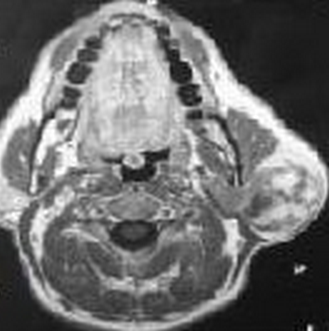

Les liposarcomes de la parotide ont été rarement rapportés chez l'adulte. Aucune association à un syndrome de Sjögren n'a été décrite dans la littérature. Patiente âgée de 48 ans, suivie pour un syndrome de Sjögren depuis 5 ans, était hospitalisée pour une tuméfaction cervicale gauche évoluant depuis 3 mois. Le syndrome de Sjögren a été retenu devant l'association d'une xérostomie, une xérophtalmie, une kératoconjonctivite au test de Rose Bengal, des anti-SSA positifs et une sialadénite stade IV de chisholm. Il était primitif vue l'absence d'une connectivite ou d'une autre pathologie associée. A l'examen, elle avait une tuméfaction de la région parotidienne gauche de 4 cm de diamètre, ferme, indolore, peu mobile, sans signes inflammatoires en regard. Le reste de l'examen ORL était sans anomalies. Elle n'avait pas d'adénopathies périphériques. L'examen biologique a retrouvé une hypergammaglobulinémie polyclonale. Une poussée de sa maladie, un lymphome ou une cause infectieuse étaient évoqués. L'échographie cervicale a révélé une formation parotidiennee hypoéchogène hétérogène bien limitée au niveau de la loge parotidienne inférieure gauche. L'IRM parotidienne a objectivé un processus hétérogène en hyposignal T1, hypersignal T2, se réhaussant après injection de gadolinium. Le bilan d'extension était négatif. Le Traitement a consisté en une parotidectomie totale gauche associée à un curage ganglionnaire homolatéral et une radiothérapie post-opératoire. L'examen extemporané était évocateur d'un liposarcome. L'examen anatomopathologique a conclut à un liposarcome dédifférencié myxoïde de haut grade de malignité. L'évolution était marquée par une rémission totale pour un recul de 3 ans.